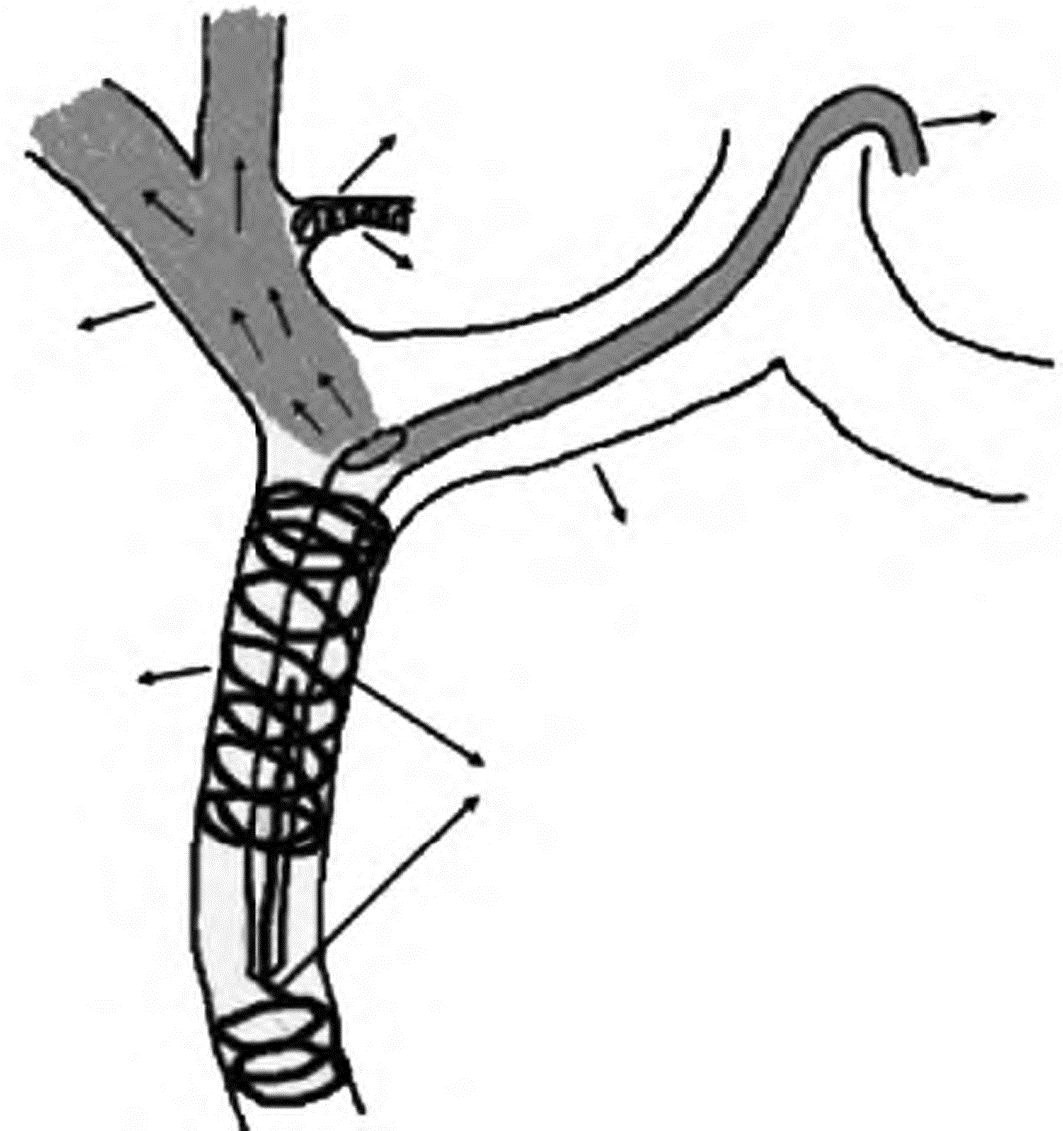

图 1 肝外血流再分布术

注:▲①腹腔动脉造影示胃右动脉(白虚线箭)从肝左动脉起始部发出,副胃左动脉(白实线箭)从肝左动脉二级分支处发出;②采用微弹簧圈超选择行胃右动脉和副胃左动脉(黑虚线箭)栓塞,胃十二指肠动脉(gastroduodenal artery,GDA)固定管头时栓塞(橙色箭),经药盒留置导管行肝动脉造影显示肝动脉分支显示完全,未见胃肠道动脉分支显示;▲③腹腔动脉造影示肝固有动脉发出十二指肠后上动脉(白实线箭)和胃右动脉(白虚线箭);④采用微弹簧圈超选择行胃右动脉和十二指肠后上动脉(黑虚线箭)栓塞,GDA固定管头时栓塞(橙色箭),经药盒留置导管行肝动脉造影示肝动脉分支显示完全,未见胃肠道动脉分支显示;▲经胃左动脉逆行栓塞胃右动脉:⑤经胃左动脉(白虚线箭)逆行超选择微导管至胃右动脉起始部(白实线箭)造影示胃右动脉;⑥微弹簧圈栓塞胃右动脉(黑实线箭),经药盒行肝动脉造影示胃右动脉闭塞,肝动脉显示完全。

Figure 1. Extrahepatic blood flow redistribution